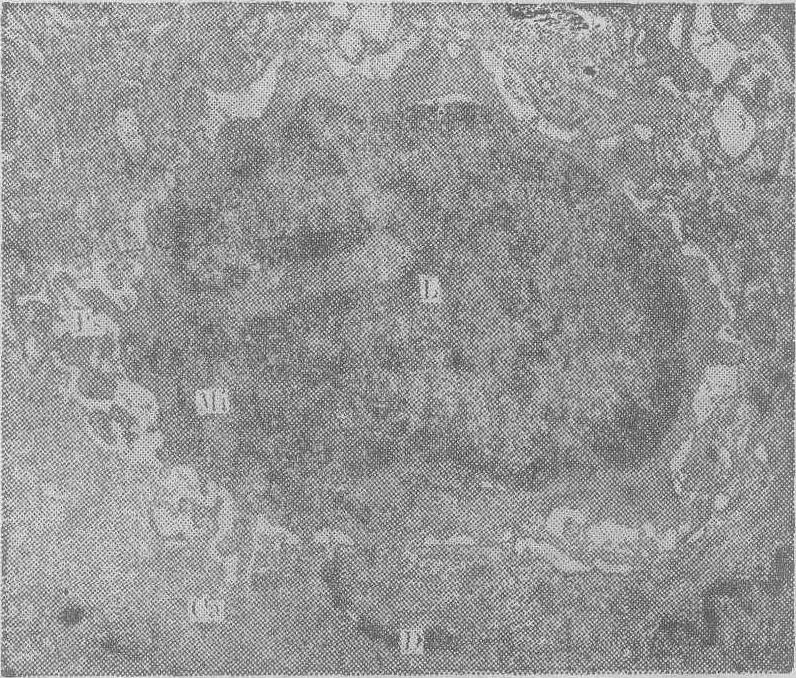

(5) 淋巴细胞: 在肿瘤组织内或肿瘤邻近的间质内,可见多少不等的淋巴细胞。此种淋巴细胞的胞质常较丰富,并有伪足样突起,胞质内线粒体亦较多,胞核的核膜常凹陷,核内异染色质丰富,少数可见核仁。在瘤组织内或其周围,与淋巴细胞相邻的瘤细胞,有时可见破坏现象即所谓“溶癌现象”(图2)。此种现象在鼻咽癌中比较明显,其他肿瘤如胃癌、肠癌、肺癌、肝癌及脑内肿瘤虽亦可见到,但程度更轻。

图2 淋巴细胞溶癌现象。图中心为一淋巴细胞(L),细胞表面有假足突起(PS),癌细胞相邻部有破坏。Mi为线粒体,D为桥粒×15000